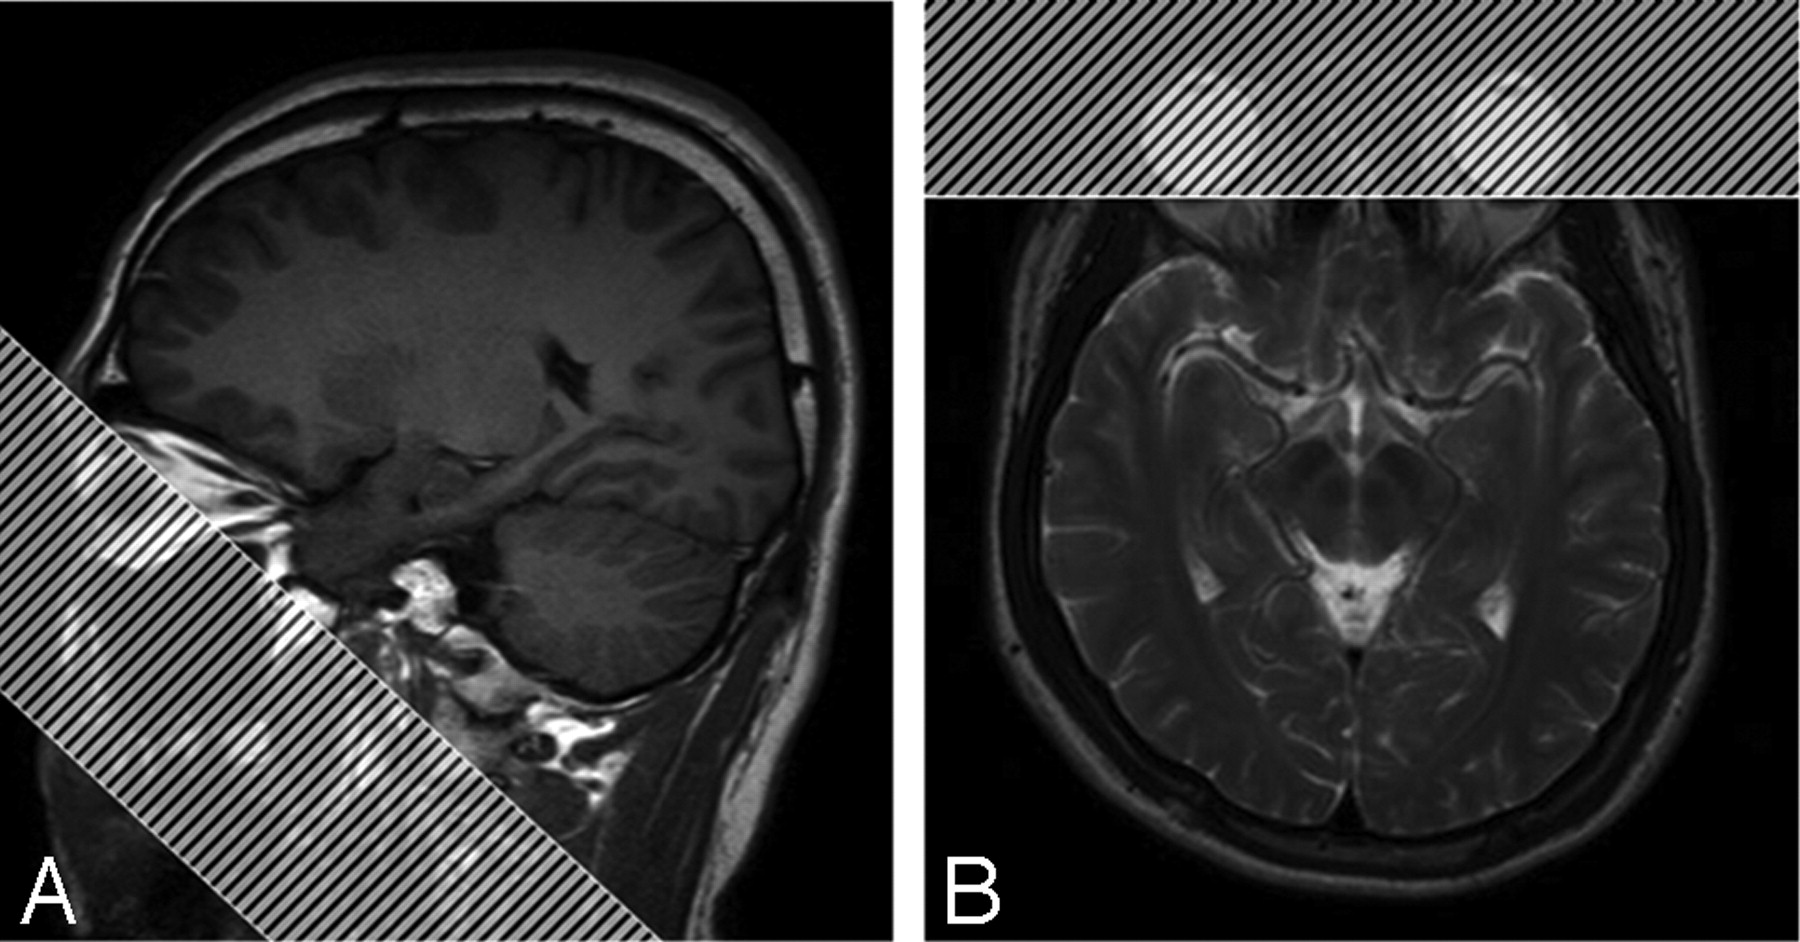

We performed experiments to investigate the phenomenon of pseudolesions from unfolding artifacts in SENSE-DTI. We acquired data on a 3T MR system. For DTI, 6 noncollinear diffusion-weighted images with a b value of 1000 s/mm2 and a single b = 0 image were acquired with TR, 6000 ms; TE, 80 ms; FOV, 25 cm; matrix size = 112 × 112; NEX = 4, and a SENSE acceleration factor R = 2, 3, and 4. To verify the source of unfolding artifacts from the distorted eyeballs, we acquired another set of images with a remedy method by applying a saturation band at oblique angulations over the eyeball region to saturate the signal intensity (Fig 2). Other than the saturation band, all parameters were kept the same as for DTI acquisition.

Sagittal (A) and axial (B) views of the saturation band applied over the eyeball regions to eliminate unfolding pseudolesions in parallel imaging. The saturation band was placed near the borderline of the skull base to avoid accidental suppression of signals from the brain tissue.